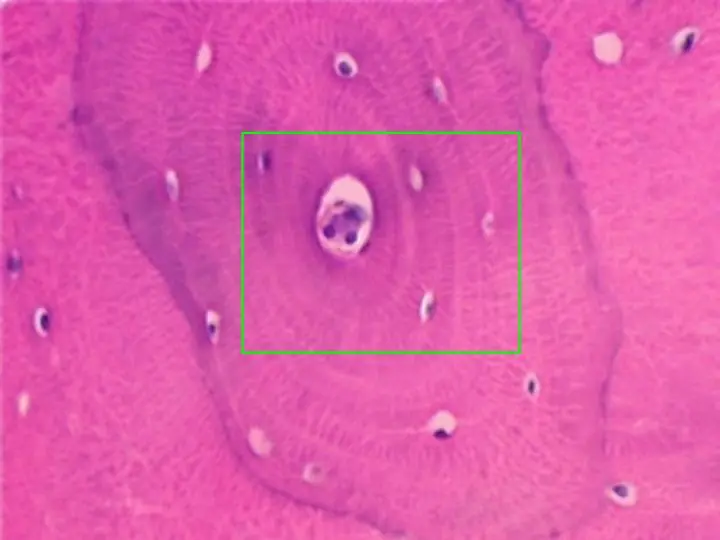

dijo:Hueso compacto, observado con el objetivo de 10x. Se aprecian varios sistemas de Havers completos, así como numerosos conductos centrales de éstos, en sección transversal. Igualmente, aparecen gran cantidad de lagunas óseas. En otra microfotografía aparece uno de los sistemas de Havers (zona encuadrada en azul) a mayor aumento

dijo:Detalle con el objetivo de 40x de un sistema de Havers. Se observa el conducto central y las lagunas óseas en cuyo interior destacan los núcleos de los osteocitos en color azul. El conducto central y parte del sistema de Havers (zona encuadrada en verde) pueden observarse a mayor aumento en otra microfotografía

dijo:Detalle con el objetivo de 100x de un sistema de Havers, con su conducto central. En torno a éste, aparecen las laminillas óseas, dispuestas concéntricamente, destacando en su interior lagunas óseas y conductos calcóforos, que las comunican entre sí y con las lagunas